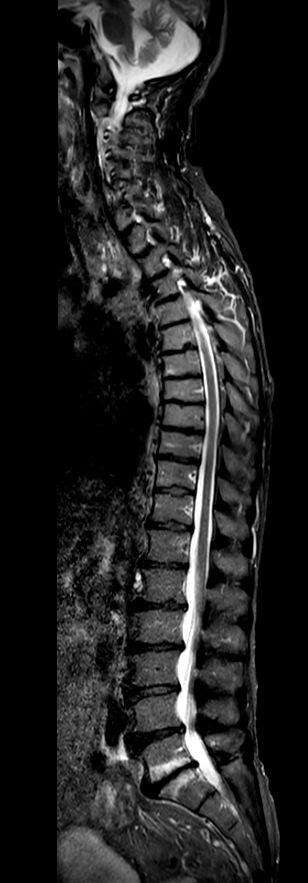

Sagittal STIR TSE (2 stations)Compressed SENSE